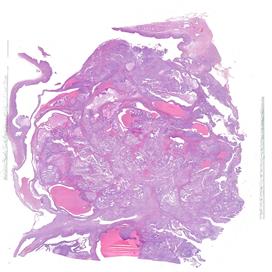

Il carcinoma sieroso ad alto grado dell’ovaio rappresenta una delle neoplasie ginecologiche più aggressive, con un alto tasso di recidiva e una sopravvivenza a lungo termine ancora limitata, nonostante i progressi terapeutici degli ultimi anni. I biomarcatori predittivi di risposta al trattamento, tra cui l’espressione del recettore dei folati (FRα), stanno emergendo come strumenti essenziali per personalizzare le terapie e migliorare gli esiti clinici delle pazienti. Il progetto nasce con l’intento di promuovere un apprendimento interattivo, coinvolgendo i partecipanti in attività mirate al miglioramento dei processi diagnostici e operativi. I patologi, infatti, rivestono un ruolo fondamentale nell’identificazione e caratterizzazione dei biomarcatori predittivi, contribuendo all’ottimizzazione dei percorsi terapeutici. L’evento, strutturato in due incontri online, si pone come obiettivo quello di fornire ai partecipanti gli strumenti teorici e pratici per l’esecuzione, la valutazione e l’interpretazione dei test di espressione dei biomarcatori. L’intento è quello di promuovere un approccio diagnostico sempre più integrato e personalizzato, ponendo l’accento sull’importanza di mantenere standard qualitativi elevati e monitorare nel tempo il proprio lavoro. Per raggiungere questo obiettivo formativo verranno messi a disposizione dei partecipanti kit specifici per esercitarsi nel perseguire la qualità e verificarla nel tempo. I risultati verranno poi discussi nella puntata finale del percorso.

OVAIO

2024 B 45509 A3 EE